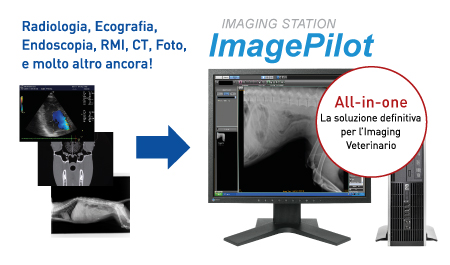

Un vero e proprio PACS!

Radiologia, Ecografia, endoscopia, RMI, CT, foto..e molto altro ancora! Non solo una stazione di acquisizione immagini! Grazie alla sua versatilità, potrai acquisire ed archiviare immagini e filmati provenienti da svariate modalità DICOM e periferiche generiche, quali Ecografi, CT, RMI, Endoscopi e macchine fotografiche.